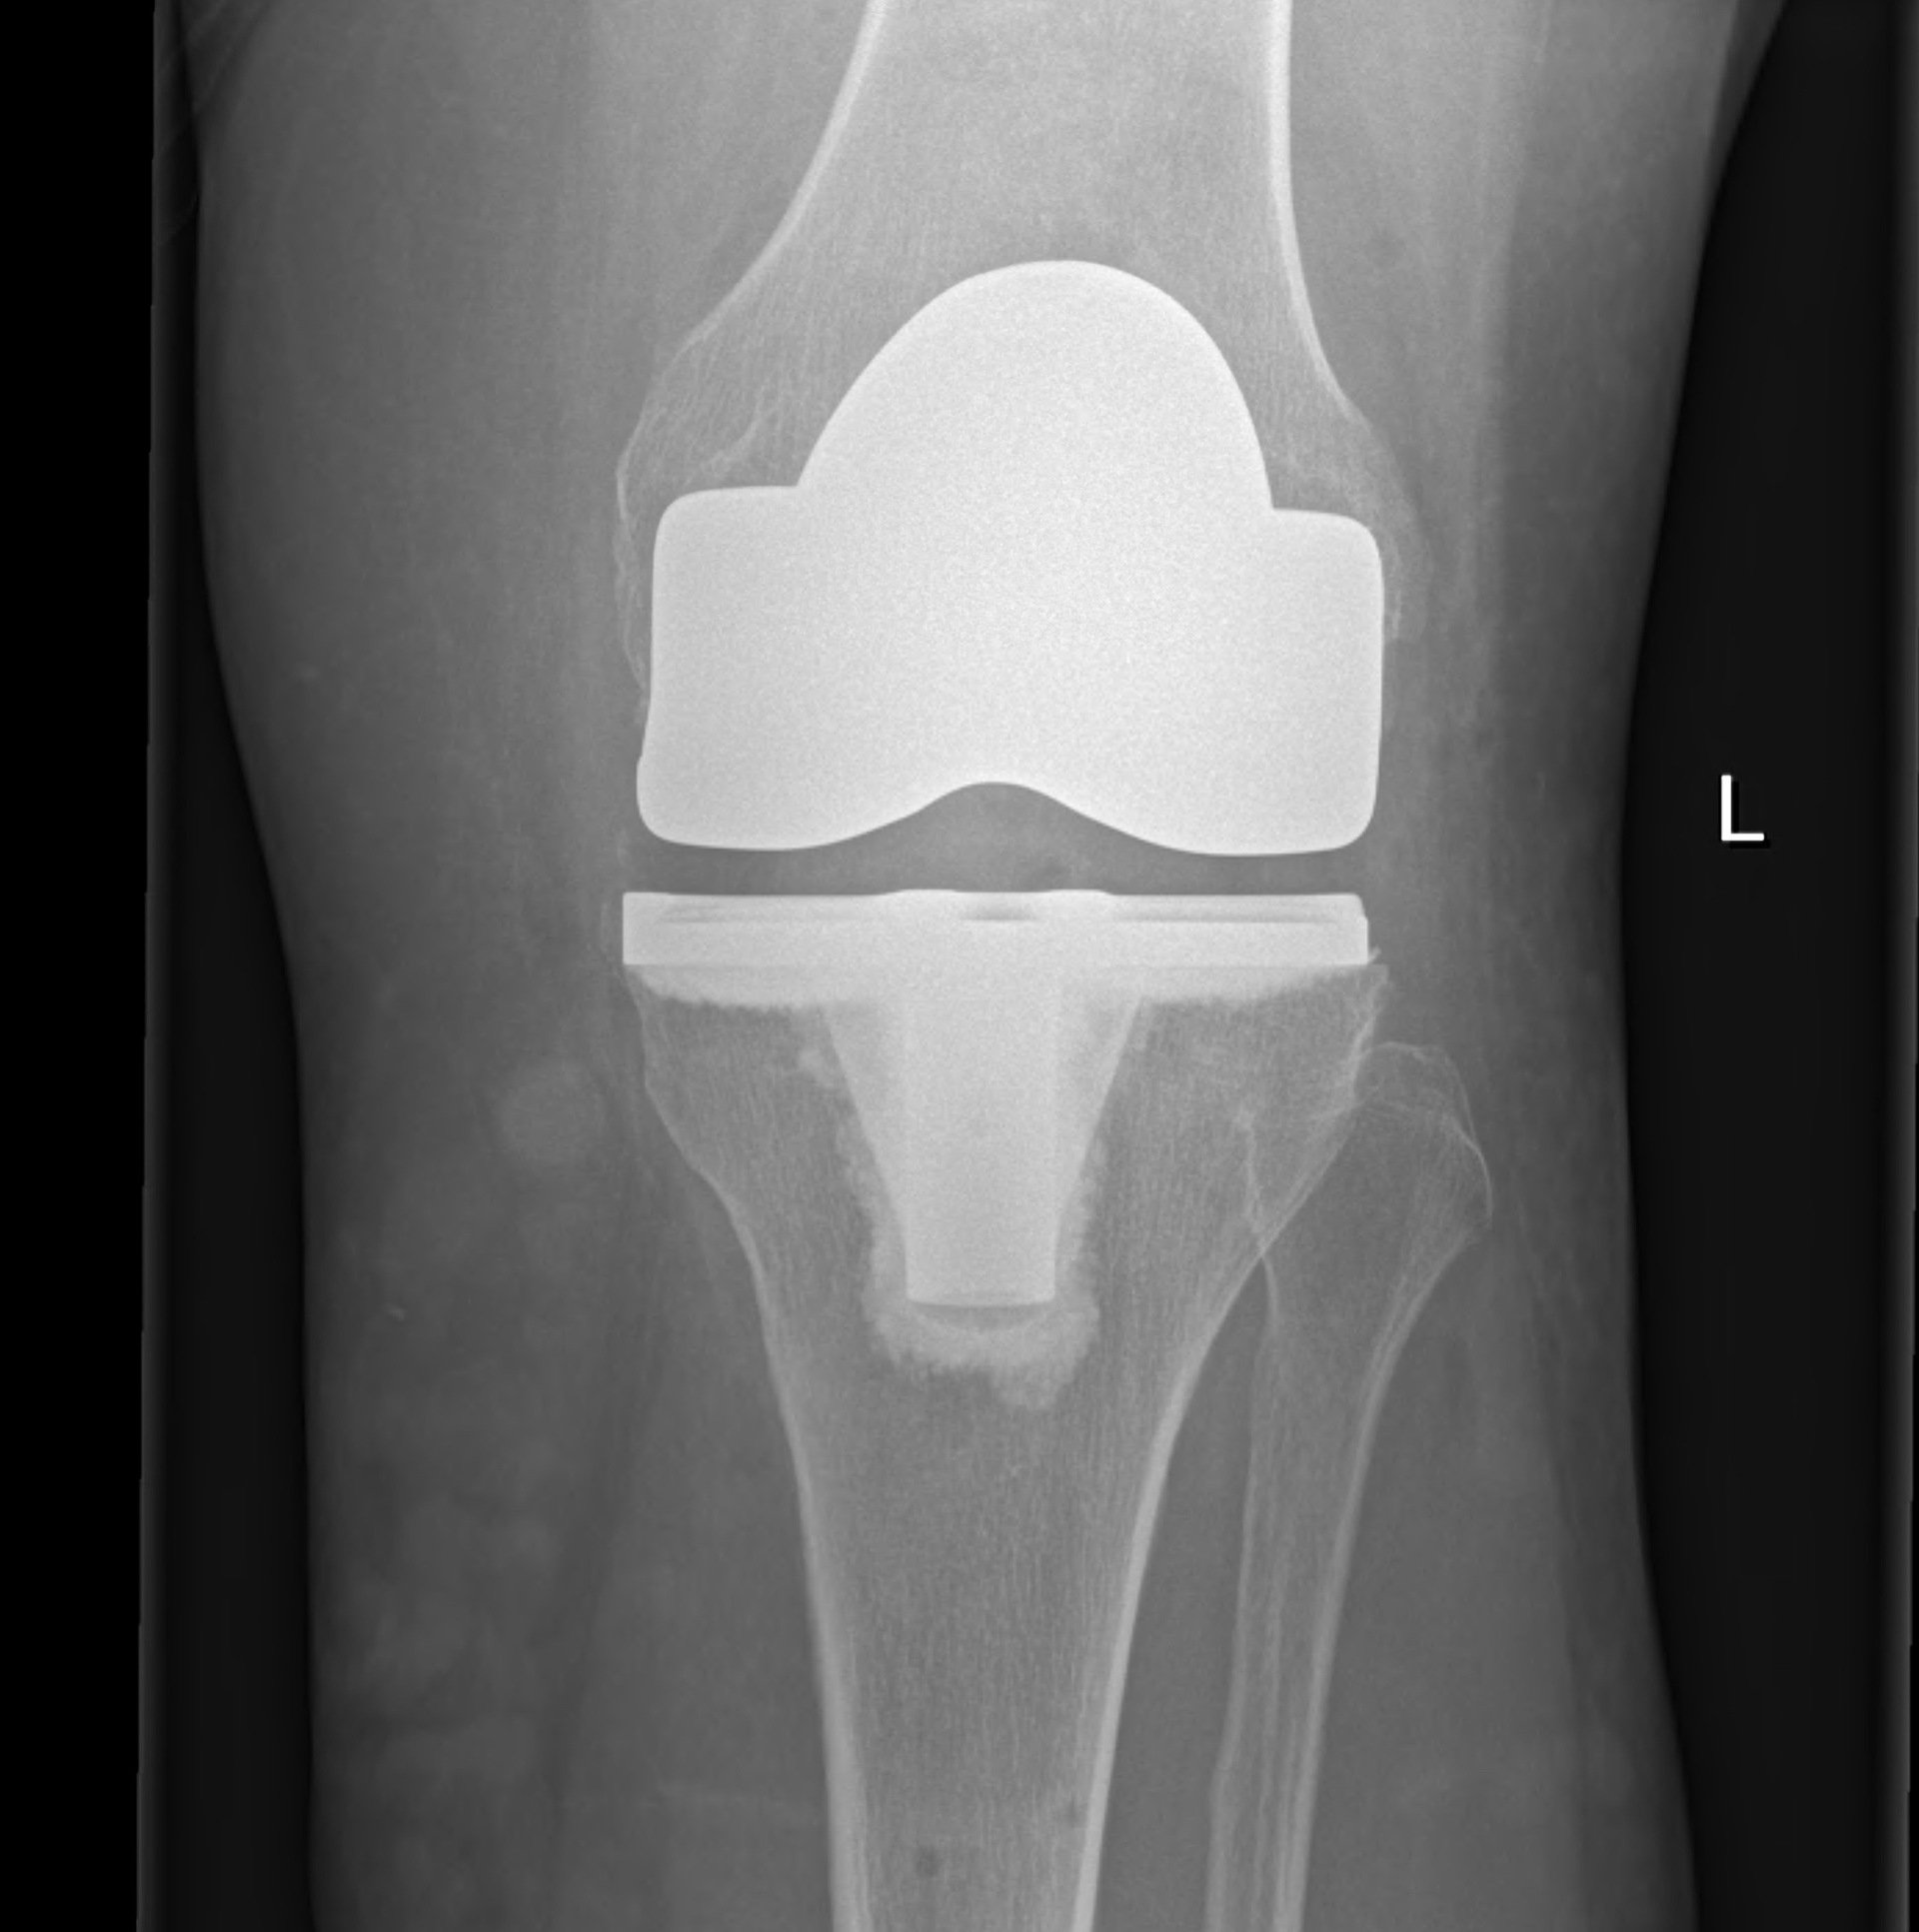

Total Knee Replacement with Stryker Navigation or OMNI RoboticAssisted